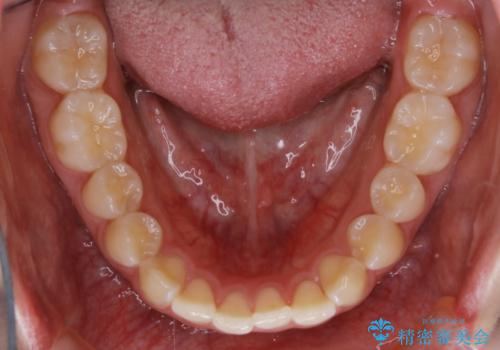

- 初診時、前歯のガタつきを主訴にご来院されました。

精密検査の結果奥歯の噛み合わせのズレからくる前歯のガタつきであることが分かり、患者様と相談した結果、全体をしっかりと治療することをご選択なさったので奥歯から動かして噛み合わせと見た目の両方を治す治療プランとなりました。

下顎の歯は幸いガタつきが少なかったため、下顎を基準とし構成する方針としました。